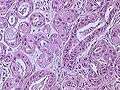

Invasive ductal carcinoma of the Breast assayed with anti Mucin 1 antibody.

Invasive ductal carcinoma of the Breast assayed with anti Mucin 1 antibody..jpg) Breast cancer (Infiltrating ductal carcinoma of the breast) assayed with anti HER-2 (ErbB2) antibody.

Breast cancer (Infiltrating ductal carcinoma of the breast) assayed with anti HER-2 (ErbB2) antibody..jpg) Histopathology of invasive ductal carcinoma of the breast representing a scirrhous growth. Core needle biopsy. Hematoxylin and eosin stain.

Histopathology of invasive ductal carcinoma of the breast representing a scirrhous growth. Core needle biopsy. Hematoxylin and eosin stain. Invasive ductal carcinoma of the breast. H&E stain.

Invasive ductal carcinoma of the breast. H&E stain.- Histopathology of invasive ductal carcinoma of the breast representing a scirrhous growth. Core needle biopsy. HER-2/neu oncoprotein expression by Ventana immunostaining system.

Histopathology of invasive ductal carcinoma of the breast. H&E stain.

Histopathology of invasive ductal carcinoma of the breast. H&E stain.